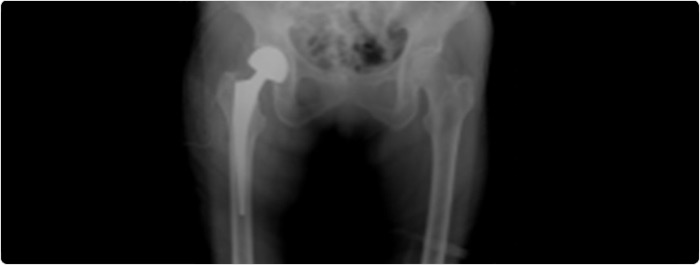

ในผู้สูงอายุที่มีภาวะกระดูกหักแบบเคลื่อนที่หรือภายในข้อ  ศัลยแพทย์อาจเลือกทำ “การผ่าตัดเปลี่ยนข้อสะโพกแบบบางส่วน โดยจะเปลี่ยนเฉพาะส่วน หัวกระดูกต้นขา (Femoral head) ด้วยกระดูกเทียมโลหะ แต่จะไม่เปลี่ยนส่วนเบ้ากระดูกสะโพก (Acetabulum)” หรือที่เรียกว่า Hemiarthroplasty โดยเปลี่ยนส่วนของกระดูกที่หักด้วยรากเทียมโลหะ อย่างไรก็ตาม สำหรับผู้สูงอายุที่มีสุขภาพแข็งแรงและยังคงมีการเคลื่อนไหวอย่างคล่องตัว การผ่าตัดเปลี่ยนข้อสะโพกทั้งหมด (Total hip replacement) อาจเป็นทางเลือกที่เหมาะสม ผู้สูงอายุที่สามารถเคลื่อนไหวได้อย่างอิสระและมีภาวะกระดูกสะโพกหักอาจได้รับประโยชน์จากการผ่าตัดเปลี่ยนข้อสะโพกทั้งหมดแทนการผ่าตัดเปลี่ยนข้อสะโพกแบบบางส่วน (Hemiarthroplasty)